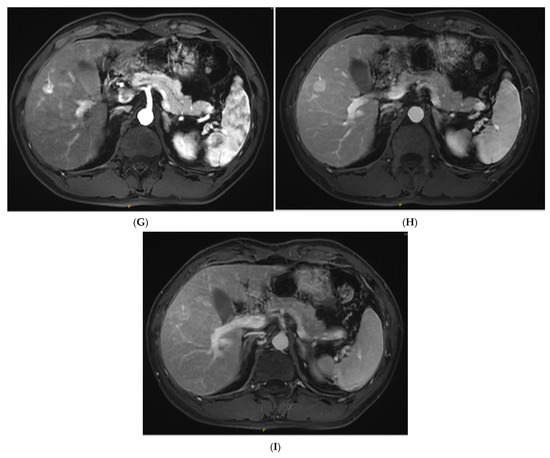

Figure 1.

The contrast-enhanced ultrasound (CEUS) and contrast-enhanced magnetic resonance imaging (CEMRI) of steatohepatitic hepatocellular carcinoma (SH-HCC). A heterogeneous hyperechoic le-sion was detected in the right lobe of the liver (A). Short linear blood flow signals were seen in the peripheral of mass (B). As seen via CEUS, the hepatic nodule did not show rim, peripheral dis-continuous or heterogeneous hyperenhancement in the early arterial phase (C). During the portal venous phase, it was continuous iso-enhancement (D). It exhibited mild washout in the late phase (E). The hepatic lesion was heterogeneous hypointense on T1WI (F). A signal drop in the T1WI opposed-phase was observed (G). It was marked as hyperintense on unenhanced T2WI (H). After injection of contrast agent, the hepatic lesion showed non-rim hyperenhancement in the arterial phase (I). It became hypo-intensity during the late phase (J).